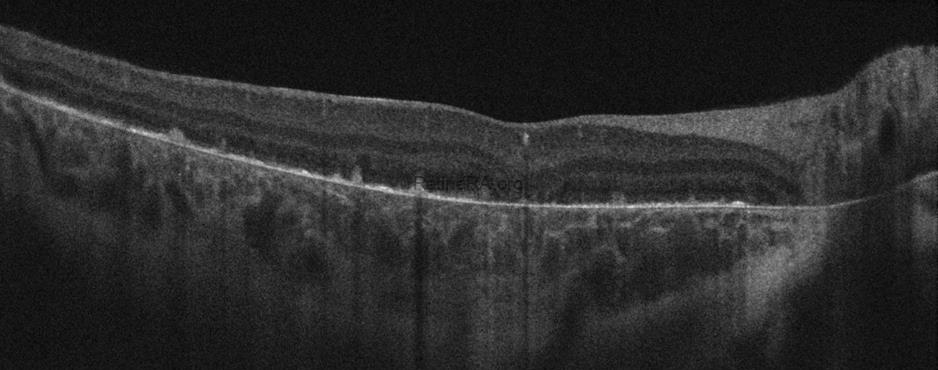

Optical coherence tomography (OCT) imaging showed bilateral hyperreflective dots in the inner retinal layers, bright reflective deposits in the RPE-Bruch membrane complex, and the absence of outer retinal tubulations. Among degenerative retinal diseases, the frequency of outer retinal tubulations is highest in Bietti crystalline dystrophy. However, retinal atrophy must be evident for outer retinal tubulations to appear. Therefore, this finding may not be seen in early-stage disease. The ellipsoid zone, interdigitation zone, and RPE disruption were more prominent on parafoveal OCT scans. The presence of prominent crystalline retinal deposits, together with the FAF and OCT findings, led to the diagnosis of early-stage Bietti crystalline dystrophy in this patient.

OCT of early-stage Bietti Crystalline Dystrophy